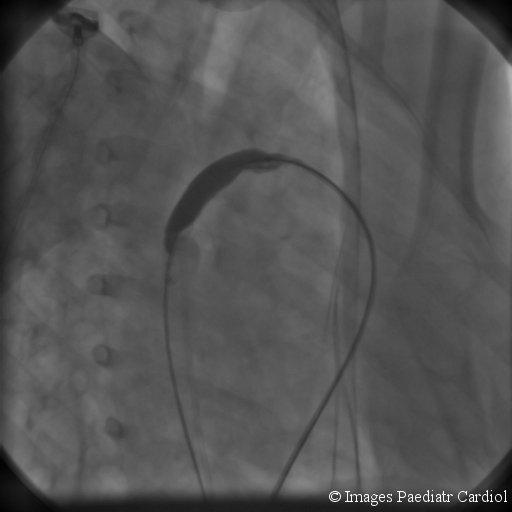

Nonsurgical closure of patent ductus arteriosus (PDA) using a duct occluder placed percutaneously is currently the first line of therapy and the success rate is quite high. Several devices are currently available. An eight year child underwent device closure of the ductus. However after deployment of the device it, became dislodged into the left pulmonary artery. Several attempts at catheter retrieval failed. The child underwent successful surgical removal of the device without cardiopulmonary bypass.

使用经皮放置的导管封堵器非手术闭合动脉导管未闭(PDA)目前是一线治疗方法,成功率相当高。目前有几种装置可供使用。一名8岁儿童接受了动脉导管的封堵器闭合术。然而,在装置植入后,它移位到了左肺动脉。多次尝试通过导管取出均失败。该儿童在未进行体外循环的情况下成功接受了手术取出装置。